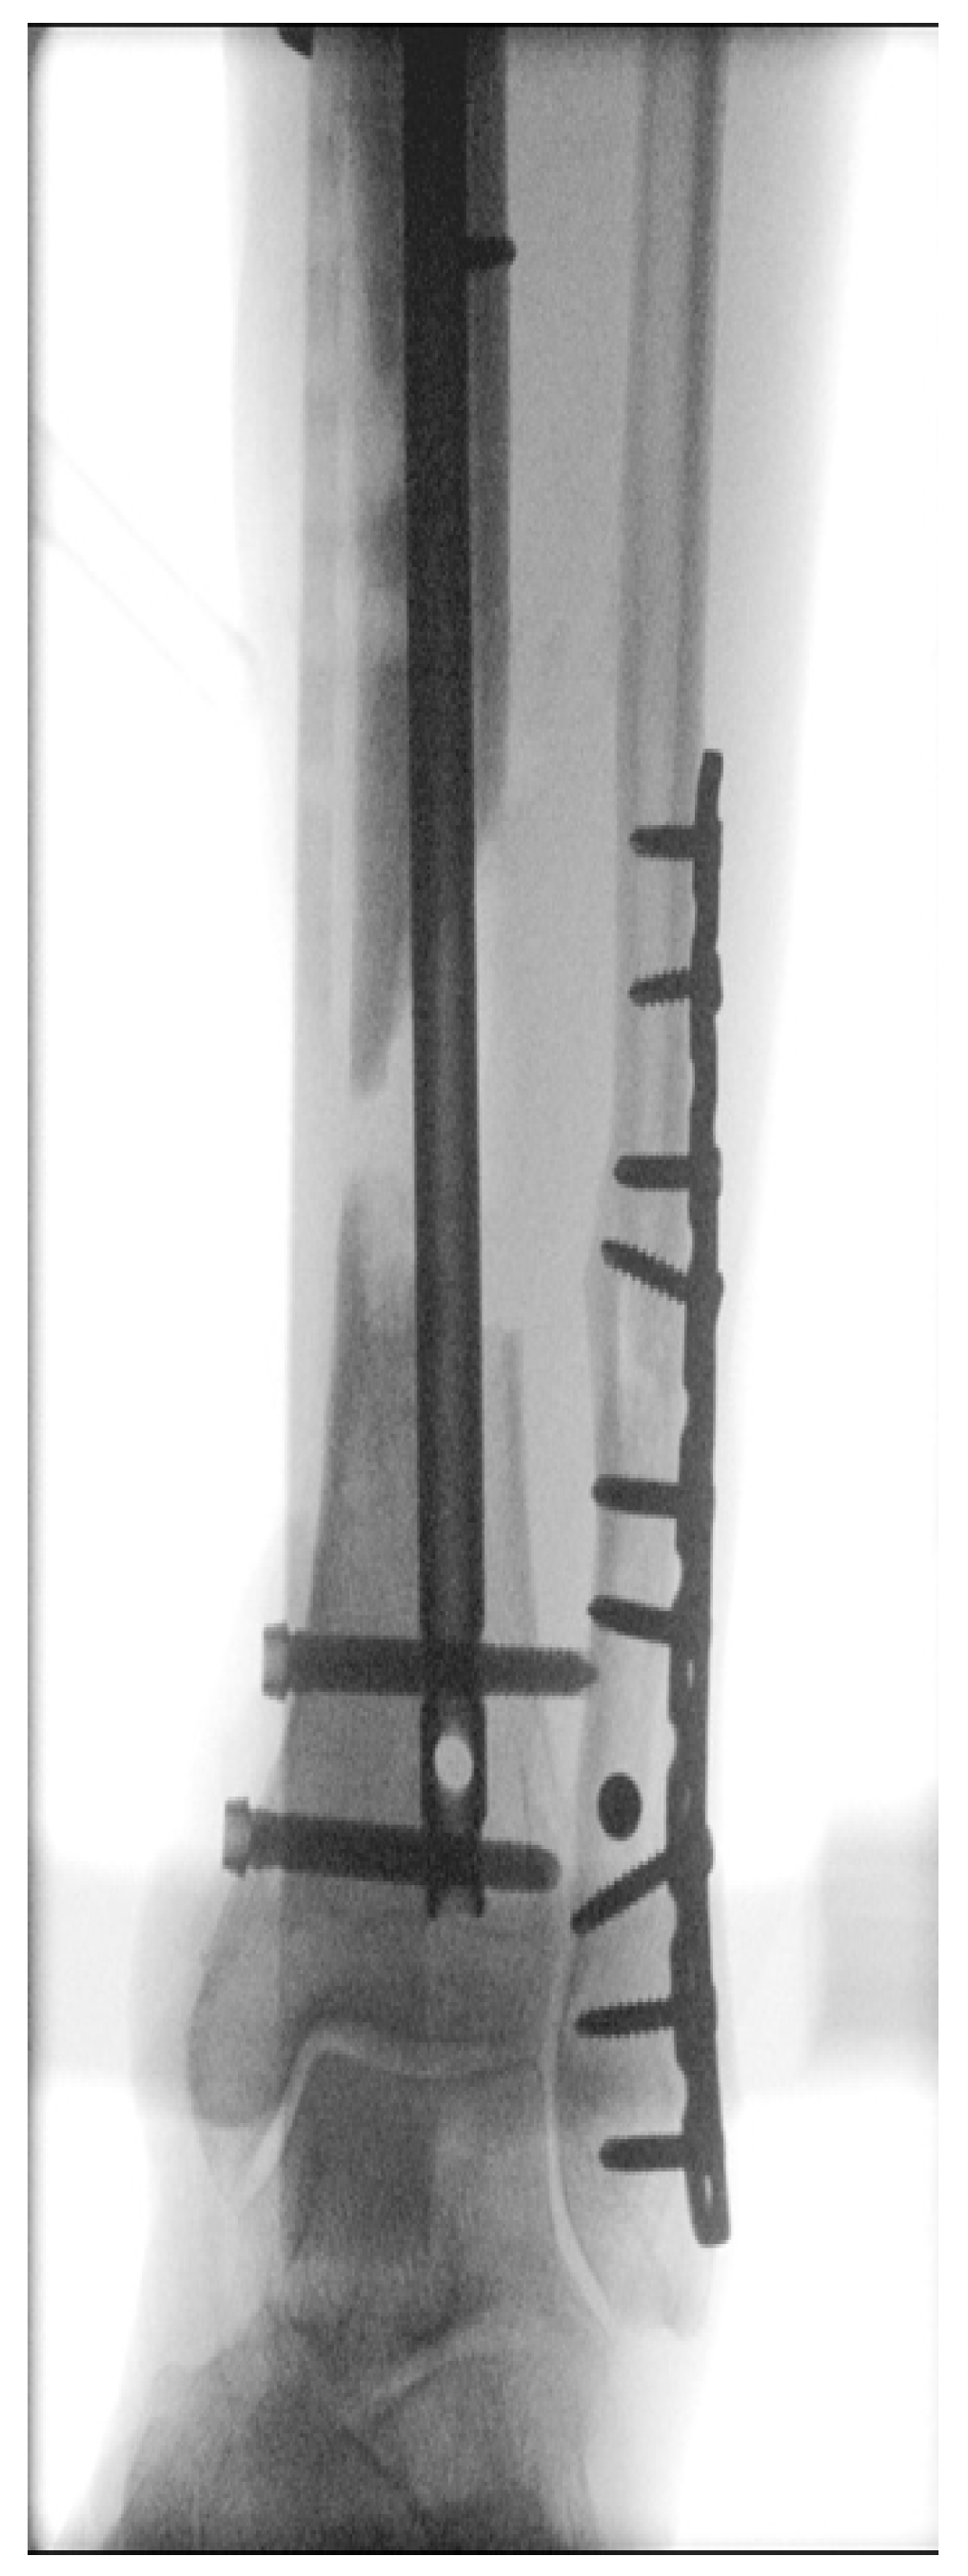

Surgical Procedures